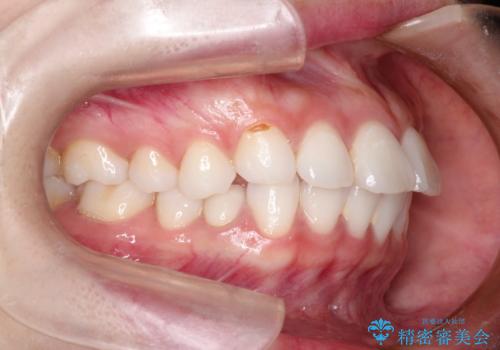

出っ歯を改善した後に真っ白な歯に 矯正歯科治療と審美歯科治療